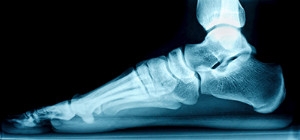

Flat feet is a fairly common foot condition. The foot appears to be flatter on the sole than it should be, as a result of a dropped arch. Many people experience discomfort from having flat feet, and other areas of the body may become affected. The majority of babies are born with flat feet, and the arch generally develops in the teenage years. This may occur in some adults, which may be for genetic reasons. Additionally, existing medical conditions may lead to developing flat feet. These can include obesity, diabetes, high blood pressure, and certain types of arthritis. It is beneficial for adults who have flat feet to rest after exercising, and it may help to wear custom made orthotics that can mimic the arch of the foot. There may be specific stretches to perform that may help the achiness of having flat feet. If you have this condition, it is suggested that you confer with a podiatrist who can help you with possible remedies for this ailment.

Flatfoot is a condition in which the arch of the foot is depressed and the sole of the foot is almost completely in contact with the ground. About 20-30% of the population generally has flat feet because their arches never formed during growth.